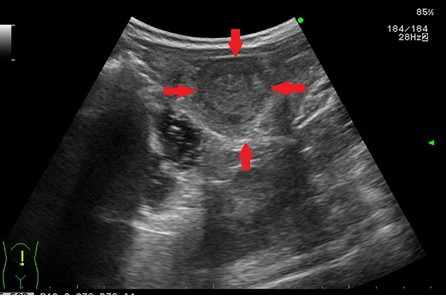

- 간암, 간종양: 실질 내부에 덩어리 유무 탐색

- 췌장암: 췌장 조직 내 종괴 관찰 가능

- 신장 종양, 낭종: 악성·양성 종양 여부 1차 판별